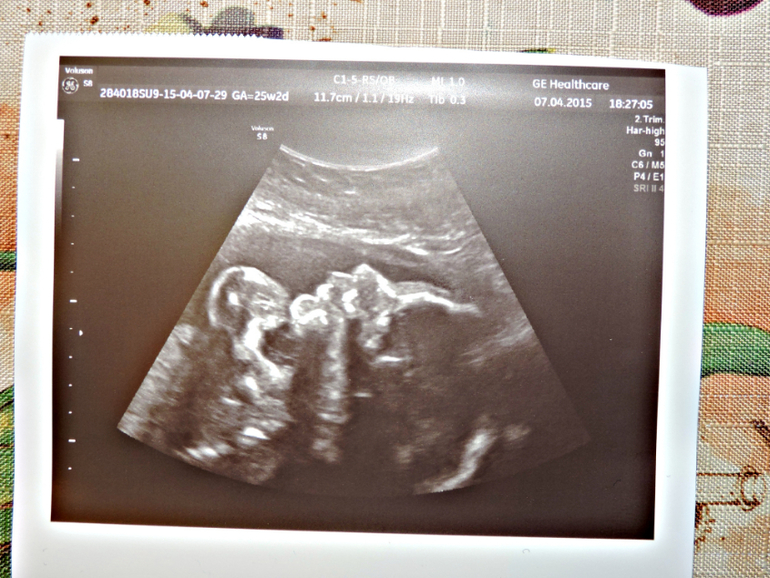

26 недель

Пузяши наши, ВДМ, тазСходила сегодня на УЗИ к Др.Озолине я просто в восторге , прекрасный врач , всё объяснила , всё показала , даже фотку дала и живот вытерла =))) и мы наконец то узнали , кто у нас будит МАЛЬЧУГАН =))) Вес его уже 780 гр , лежит головкой вниз , спинкой и попой с левой стороны живота и ножки наверху я прям пальчики видела на ножках , носик , губки и ещё у нас обвитие пуповины вокруг животика , но врач сказала , что обвитие лёгкое и ещё распутается , хотя меня мама родила с обвитием =) вообщем такой у нас был поход и теперь только к ней буду ходить =)